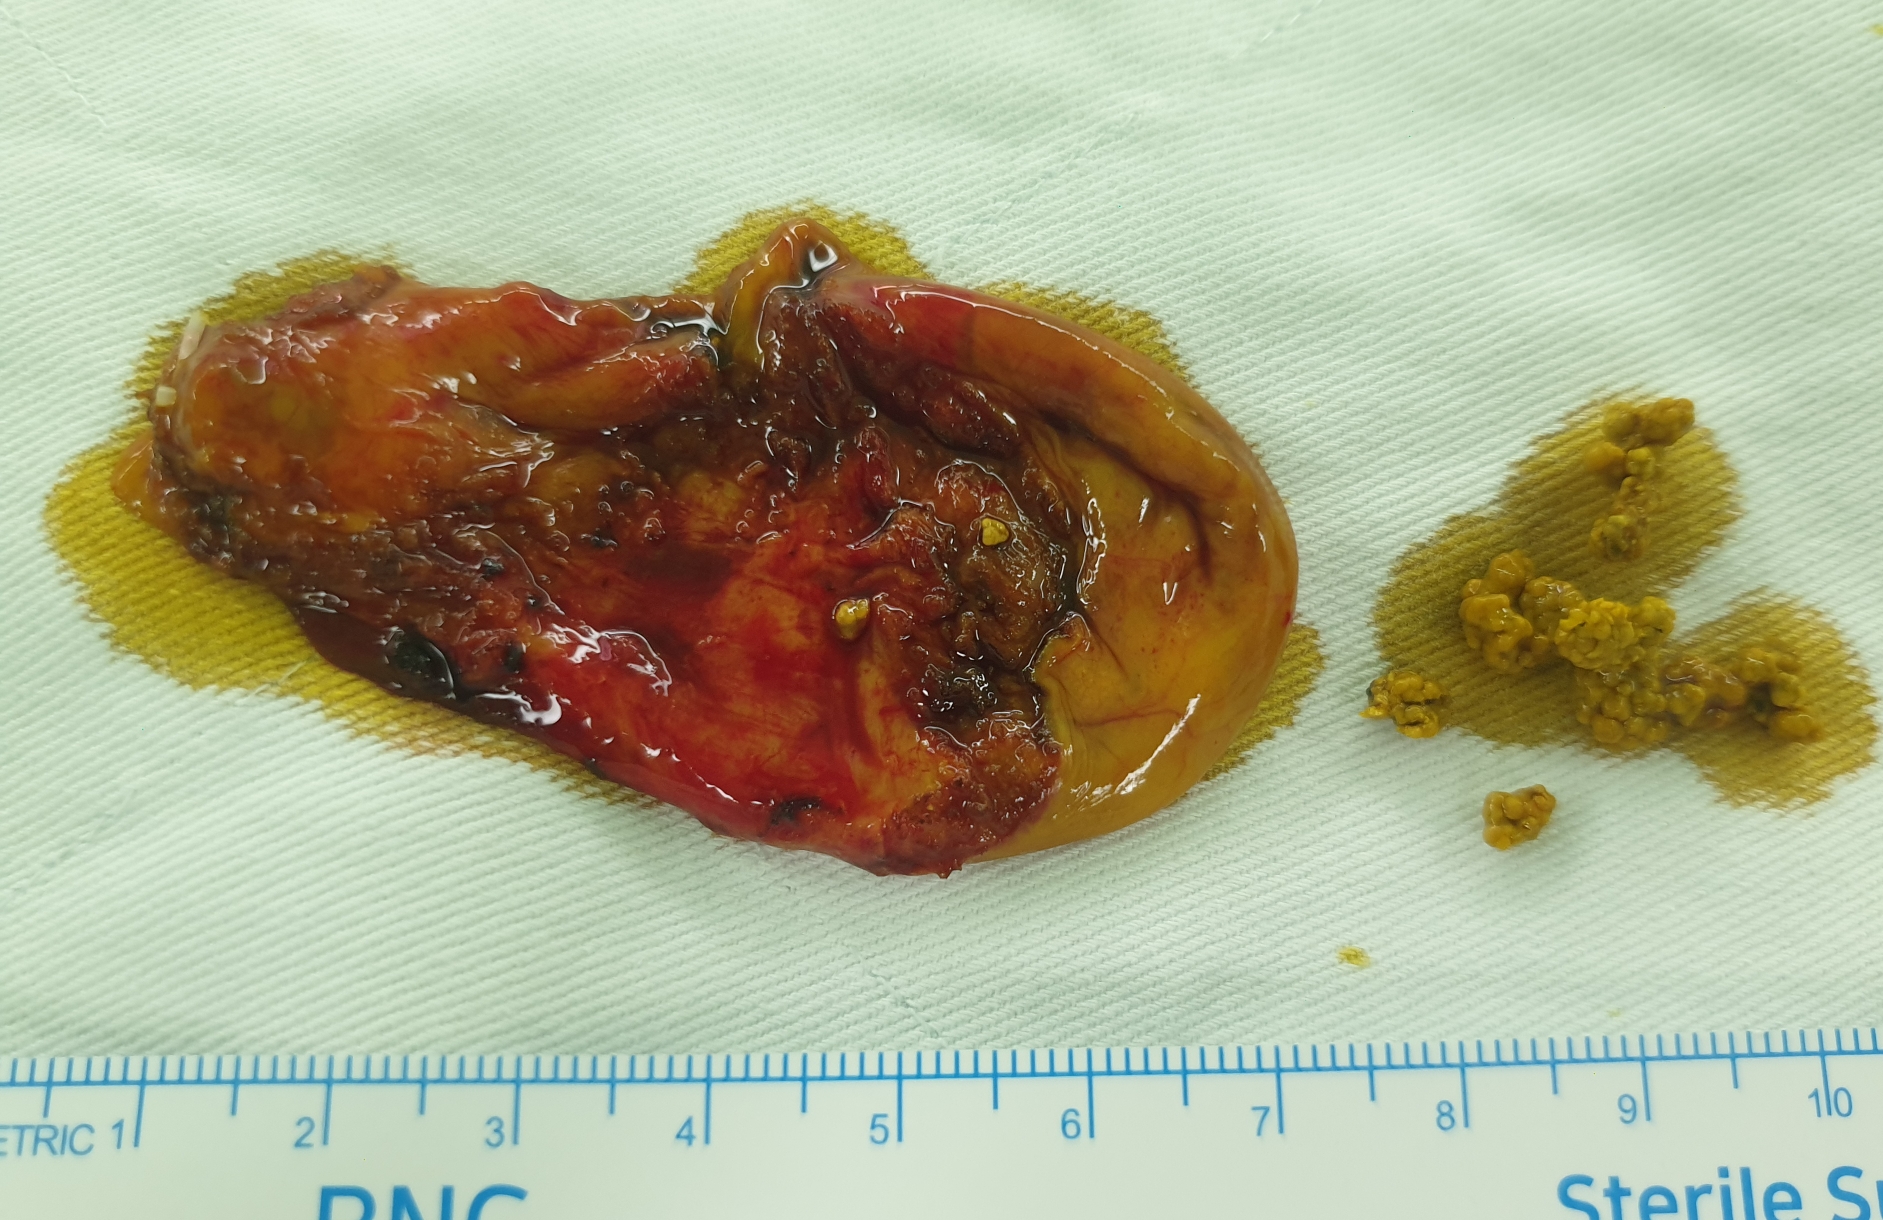

상복부 통증으로 여성아이병원에서 초음파를 시행 후 담석증에 의한 통증으로 확인되어 방금 복강경 담낭 절제를 시행했습니다.

수술은 25분 걸렸습니다.